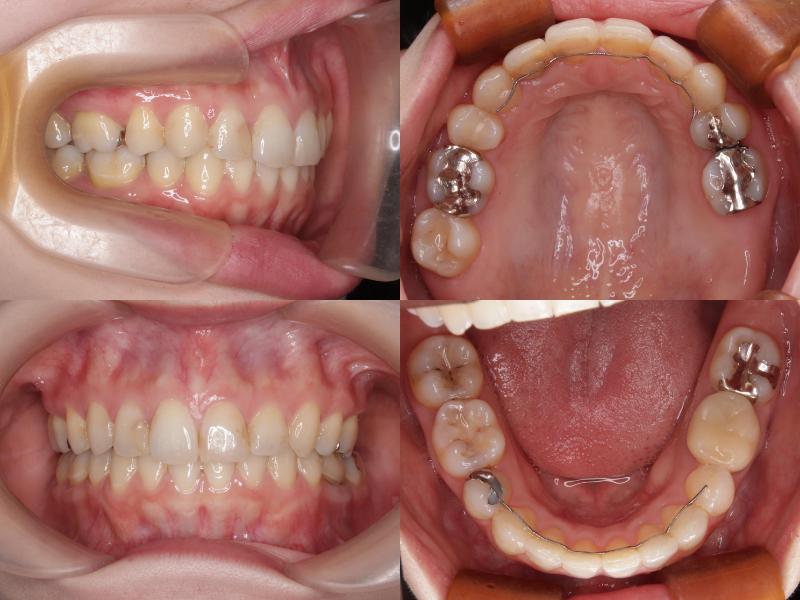

左上7番は再根管治療を行いできるだけ保存しましたが、矯正治療途中で症状が悪化したため抜歯となりました。

治療期間:2年7ヵ月

左上7番は再根管治療を行い経過観察としていましたが、治療途中で症状が悪化したため抜歯となりました。

治療の結果、口元の突出感とディープバイトの改善が認められ、より自然で調和のとれた横顔を得ることができました。